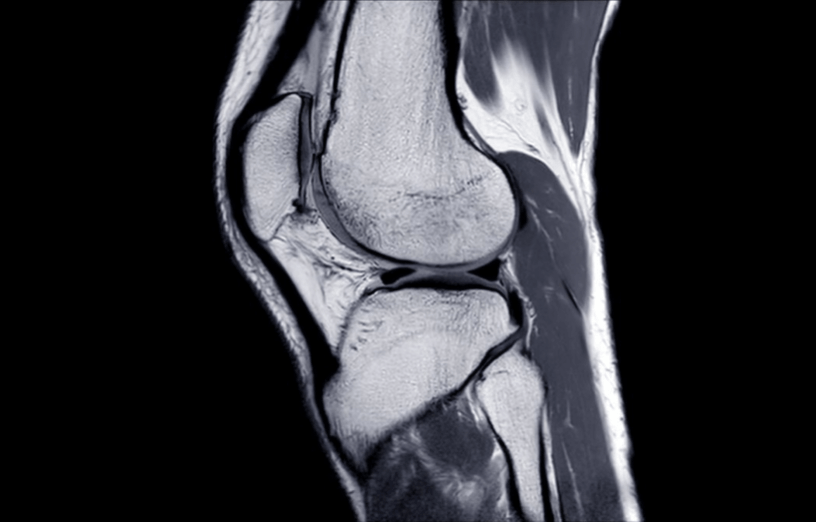

more »Not Just a ‘Knee-jerk’ Reaction:

The Surprising Causes of Your Knee Pain (and What to Do About It!) Knee pain isn’t just an issue for athletes or those who forgot they’re not 18 anymore. It can affect anyone and make simple tasks—like walking, squatting, or getting off the sofa—feel like an extreme sport. The location of your pain gives a […]